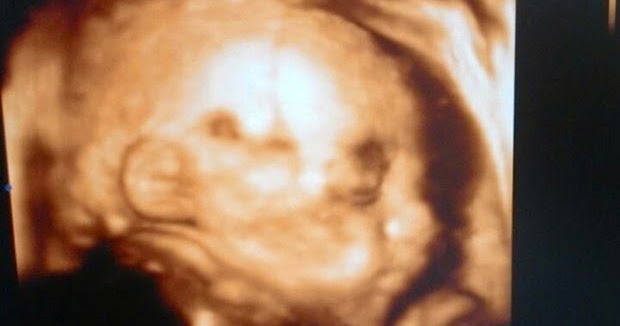

Pengalaman Bersalin Induce Sampai 3 Kali !! Merasa Induce Ubat, Belon. - Simpan

Induce Bersalin Sebanyak 22 Kali Melahirkan Bayi Yang Sudah Tiada. Induce bersalin - Unduh

Bersalin Induce Ketahui Sebab, Risiko & Tips Untuk Mengelakkannya. Bersalin induce - Unduh

Bersalin Induce? Ini Kaedah, Risiko & Persediaan Untuk Bakal Ibu. Induce bersalin persediaan kehamilan kelahiran membolehkan paksa kena antara diabetes sila hamil punca - Muat Turun

Kenapa Perlu Induce Bersalin Fakta, Risiko & Pengalaman. - Simpan

Cepatkan Bersalin Dengan JenisJenis Induce Ubatan Dan Semulajadi Ini. - Download

Kenapa Ada Doktor Guna Induce & Ada Doktor Tak Guna Semasa Bersalin. Bersalin induce guna doktor kaedah semasa kenapa jawapannya - Simpan